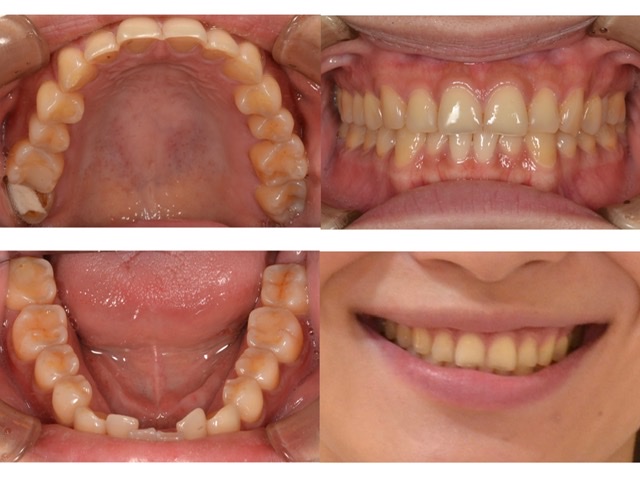

全体的に見て欲しい30代女性2024.4.26

全体的に診てほしい

主訴全体的に診てほしい

診断名審美障害

年齢30代女性

治療方法前歯部部分矯正インプラント治療セラミック治療歯周治療

抜歯部位非抜歯

治療期間3年

治療費前歯部部分矯正 60万円インプラント治療 50万円/1本セラミック治療 20万円/1本歯周治療 23万円  (全て税別)

リテーナー不使用による矯正治療の後戻り歯ぎしりや過剰な噛み締めによるセラミックの破損